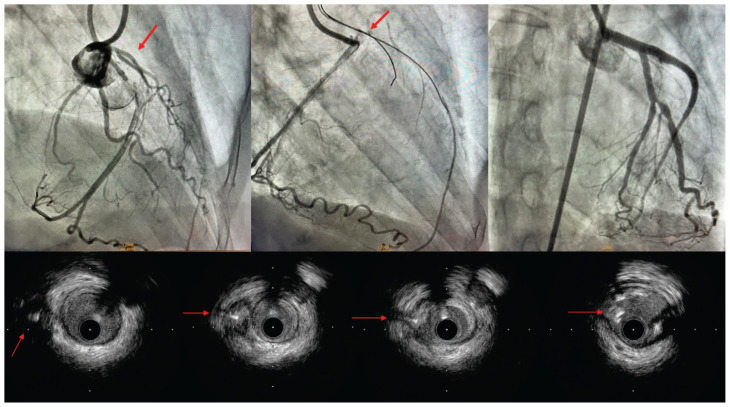

IVUS-guided cap puncture of a stumpless chronic total occlusion with sliptream technique.

Mohsen Mohandes, Cristina Moreno, Luis Mauricio Torres, Humberto Coimbra, José Luis Ferreiro